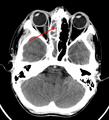

Maxillary sinusitis caused by a dental infection associated with periorbital cellulitis